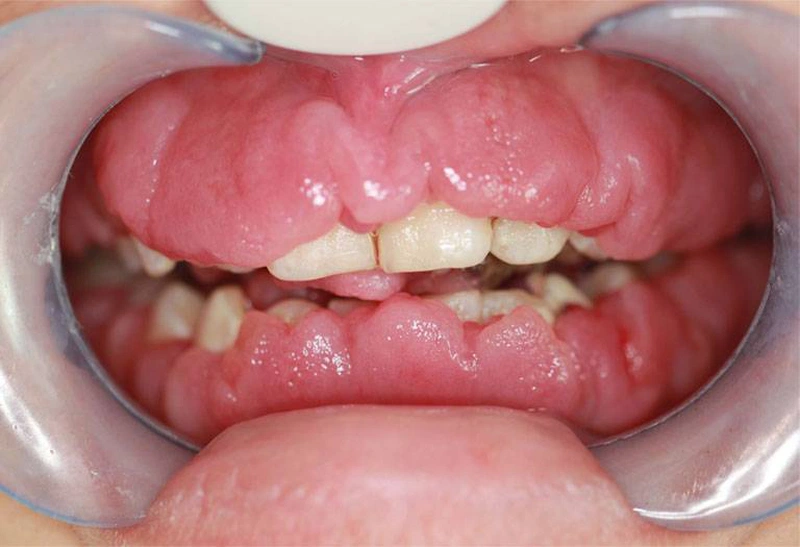

Viêm lợi phì đại là một tình trạng bệnh lý đặc trưng bởi sự tăng sinh quá mức của mô nướu. Từ đó dẫn đến hiện tượng nướu dày lên, sưng nề và có thể bao phủ một phần thân răng. Hiện tượng này thường là kết quả của phản ứng phì đại của mô lợi. Phản ứng này xảy ra đối với các tác nhân kích thích tại chỗ. Phổ biến nhất là mảng bám vi khuẩn còn mắc trong kẽ rằn. Đây là một yếu tố nguy cơ hàng đầu trong các bệnh lý nha chu.

Ngoài ra, tình trạng này cũng có thể phát sinh do tác dụng phụ của một số loại thuốc. Đặc biệt là các nhóm thuốc như thuốc chống động kinh (ví dụ: phenytoin). Ngoài ra là thuốc ức chế miễn dịch (cyclosporin), thuốc chẹn kênh canxi (như nifedipine). Tình trạng phì đại mô nướu không chỉ gây ảnh hưởng nghiêm trọng đến yếu tố thẩm mỹ. Điều này thể hiện qua việc nó làm cho răng trông ngắn hơn. Thậm chí khiến nướu chuyển sang màu đỏ đậm hoặc tím tái. Nó còn tác động tiêu cực đến chức năng sinh lý của khoang miệng.

- Nướu bị phì đại rõ rệt, phồng lên quá mức so với bình thường. Màu sắc nướu chuyển từ hồng nhạt sang đỏ tươi hoặc tím thẫm. Điều này phản ánh tình trạng viêm cấp tính hoặc mạn tính.

Tăng sản nướu có yếu tố di truyền, hay còn gọi là u xơ nướu di truyền, là một nguyên nhân đặc biệt dẫn đến viêm lợi phì đại. Đây là tình trạng mô liên kết của nướu phát triển quá mức do đột biến gen. Điều này thường xuất hiện từ giai đoạn mọc răng sữa. Thậm chí có thể kéo dài đến khi hoàn thiện hàm răng vĩnh viễn.

Ở giai đoạn đầu, u xơ nướu có thể không gây triệu chứng đau đớn rõ rệt. Điều này khiến người bệnh và phụ huynh khó nhận biết. Tuy nhiên, nếu không điều trị sớm, mô nướu sẽ dần bao phủ thân răng. Từ đó gây cản trở nghiêm trọng đến chức năng ăn nhai, phát âm. Cùng với đó là vệ sinh răng miệng và cả sinh hoạt hàng ngày. Trong một số trường hợp nặng, can thiệp phẫu thuật nướu là cần thiết. Thông qua đó phục hồi chức năng và thẩm mỹ.